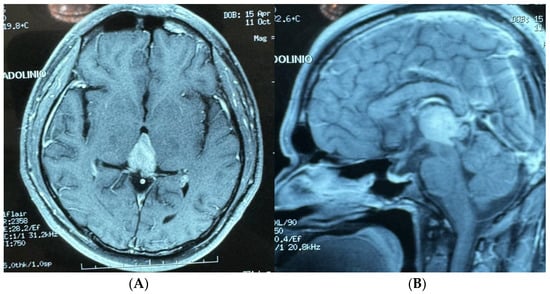

- Case 1: The AR-assisted retrosigmoid approach facilitated an 80% subtotal resection of a complex infratentorial meningioma, resulting in significant symptomatic relief and minimal postoperative complications. This underscores the potential of AR to enhance surgical outcomes in challenging anatomical regions (on the sigmoid and transverse sinuses). (Figure 1 and Figure 2). The patient’s rapid recovery and favorable outcome further emphasize the clinical advantages of AR-guided surgery.